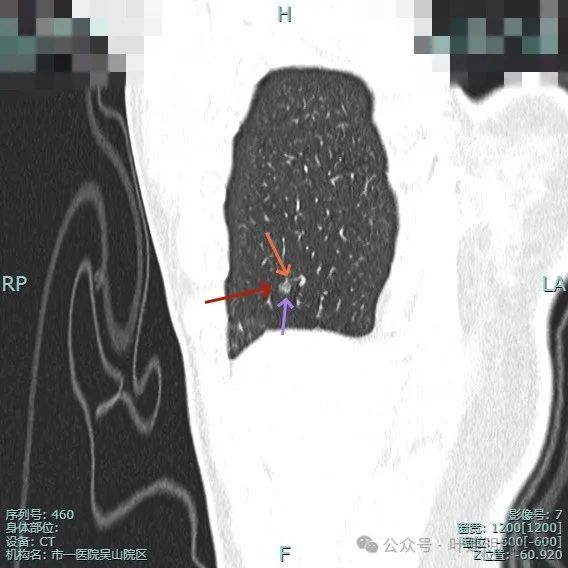

左侧病灶10:

病灶表面不平有分叶与凹凸,密度也不均匀,有点状实性成分,邻近胸膜(叶间裂)。

表面有毛刺,灶内有小空泡征,边缘毛糙不平,密度显得不均匀。

部分边缘有毛刺或小棘突,病灶边上有扩张的细支气管,整体内部密度欠均匀。

边缘毛糙,血管进入,灶内密度显得杂乱。

有扭曲的血管进入血管,表面有凹陷与分叶。

密度不太纯,表面不平,血管有异常增粗。

胸膜有轻微牵拉,表面不平,多处微小血管进入,整体密度显得不匀。

血管征明显、灶内小空泡征、胸膜牵拉、边缘细毛刺征。

整体看上去密度不均、边缘不平、灶内空泡征以及细毛刺征均明显。